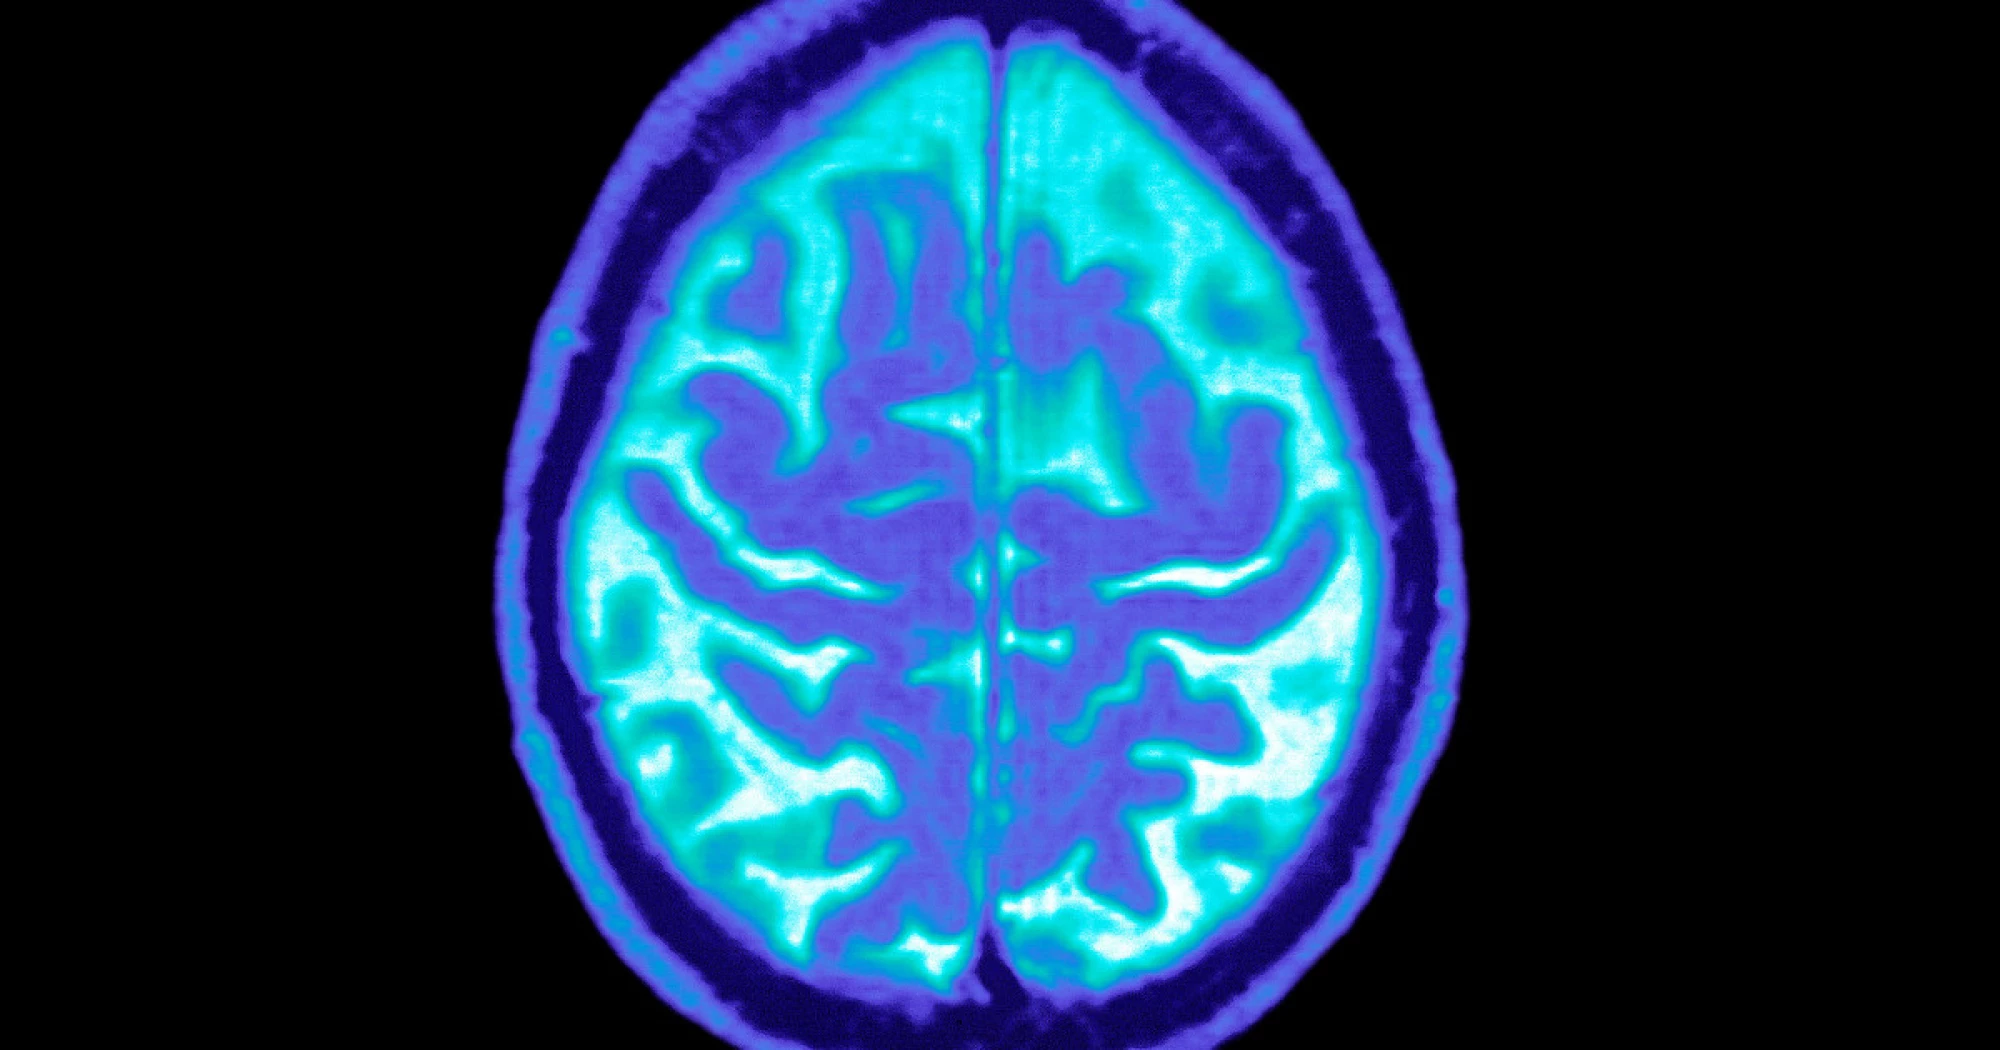

While GLP-1 drugs have become synonymous with dramatic weight loss, they’ve also become one of the most closely watched experimental approaches for slowing Alzheimer’s, a disease with few treatment options.

Scientists have spent years studying how GLP-1 medications affect inflammation, metabolism and blood vessels in the brain — factors long suspected to contribute to Alzheimer’s, said Donna Wilcock, the director of the Center for Neurodegenerative Disorders at the Indiana University School of Medicine. Obesity and diabetes — both treated by GLP-1 drugs — are also risk factors for Alzheimer’s and can cause changes in the brain that look similar to the disease.